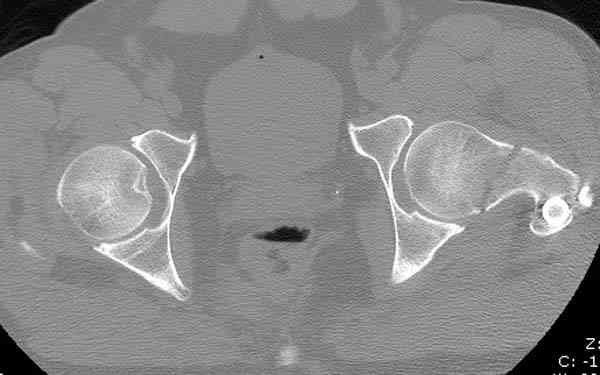

На второй день (7) обнаружен пропущенный перелом,

сделаны Компьютерная Томограмма

и проведены шурурпы через и спереди штифта без удаления.